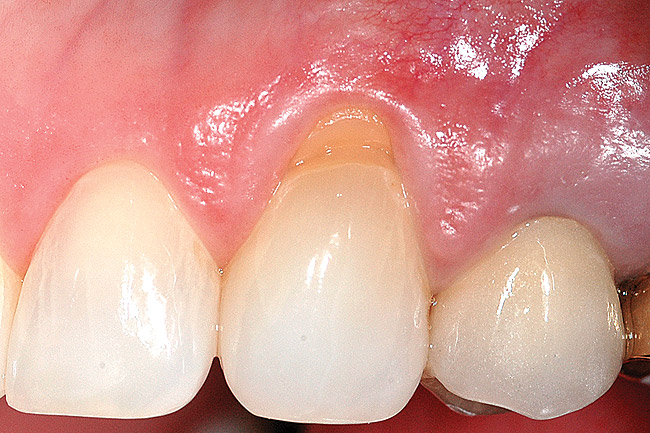

Fig 8 and Fig 9. Non-carious cervical lesions of moderate depth, Miller Class III gingival recession, absence of attached gingiva, shallow vestibule, and extrusion of the central incisors.

Figure 9